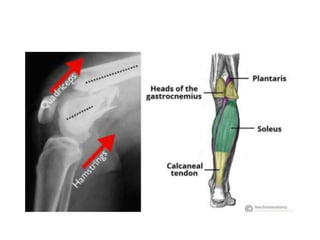

Path mechanics

When the distal femur breaks, both the hamstrings and

quadriceps muscles tend to contract and shorten.

When this happens the bone fragments change position and

become difficult to line up with a cast.

gastrocnemius: extends distal fragment (apex posterior)

adductor Magnus: leads to distal femoral Varus

Path mechanics When thedistal femur breaks, both the hamstrings and quadriceps muscles tend to contract and shorten. When this happens the bone fragments change position and become difficult to line up with a cast. gastrocnemius: extends distal fragment (apex posterior) adductor Magnus: leads to distal femoral Varus